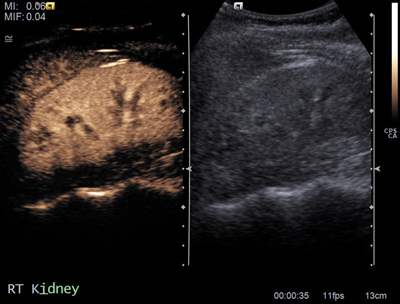

Figure 2a: US shows isoechoic central lesion.

Figure 2b: Contrast US shows same enhancement as renal parenchyma.

Columns of Bertin

Columns of Bertin (Figure 2) are hypertrophic bands of cortical tissue that separate pyramids of renal medulla. More common in the left kidney, they are positioned between upper and middle calyces. They are present in ~50% of people, and are bilateral in 20%. A double column in one kidney is rarer, occurring in only 4%. They are asymptomatic and usually found as an incidental finding on imaging. They can easily be mistaken for a renal mass on US, and other differentials include renal scarring or fetal lobulation. Thus correctly identifying this variant is essential for preventing unwarranted intervention [6].

Commonly seen on ultrasound, the normal renal contour will be displayed, and the column of Bertin will be isoechoic with the renal cortex, unlike a renal mass [7]. US may demonstrate splaying of central sinus echoes. The variant can also be distinguished by use of colour and power Doppler, which will show flow similar to the renal cortex [3]. This is sufficient to distinguish a column of Bertin from renal pathology. If the variant is detected first on unenhanced CT it will appear as a mass continuous with renal cortex, with lateral indentation of renal sinus, and deformed adjacent calyces and infundibula. With the addition of contrast, especially in the corticomedullary phase the column of Bertin can clearly be seen enhancing similarly to the normal renal cortex [7].